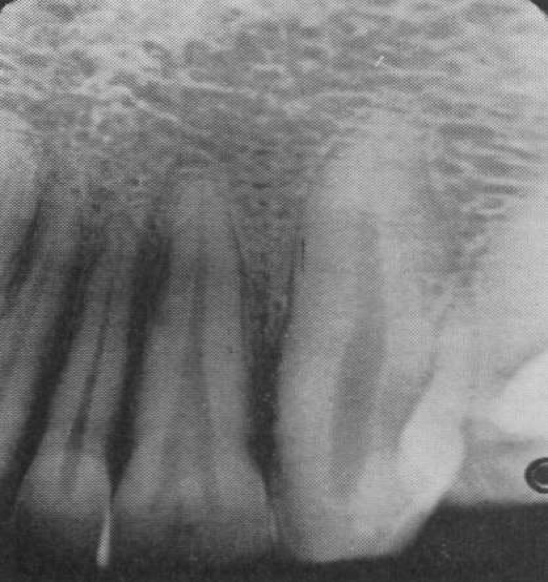

Hypercementosis

Excess cementum formation